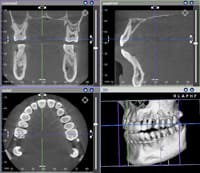

「三次元画像」の取得で、より精度の高い診察を

従来のX線写真で得られる情報は二次元の平面的なものでしたが、歯科用CTでは、短時間で三次元画像を構築できるので、より正確な多くの情報が得られることになりました。 そのため、矯正歯科治療を始めるにあたって、たとえば、骨の中に埋もれて生えてこない歯(埋伏歯)の位置を確認したり、歯周病の患者さんの歯槽骨の状態の確認などを正確に行うことができ、これらの情報は治療方針を立てる上で重要になります。

また、実際に矯正歯科治療が始まって歯の移動を行う際、より適切で安全な治療を行うことができます。歯の排列に当たっては、歯槽骨の中にしっかり歯の根を移動させる必要があります。無理な排列によって歯根が吸収したり、歯肉退縮や歯根が露出したりすることがないように必要に応じて確認を行っています。